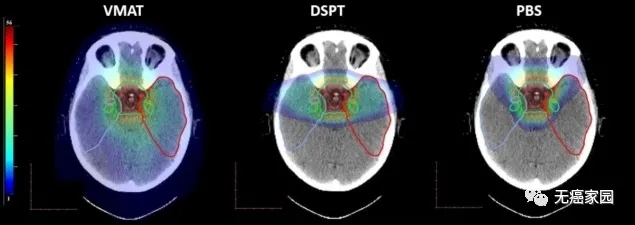

该研究比较了三种类型的放射治疗,包括两种形式的先进治疗方法,用质子粒子束照射,分别是双散射质子疗法(DSPT)和笔束扫描质子放疗(PBS),另外一种是体积调强电弧疗法(VMAT)——一种先进的常规放疗手段。

科学家发现,笔束扫描质子治疗最有可能使大脑区域对记忆仍起重要作用,也就是说笔束质子放疗治疗脑瘤时,对儿童大脑的记忆功能没有影响。

丹麦研究人员对10名接受过大脑肿瘤治疗的儿童进行了详细研究。该团队使用CT(计算机断层扫描)和MRI(磁共振成像)扫描来确定儿童大脑中的30个结构受到不同形式放射治疗的影响程度,结果发现笔束质子治疗对儿童大脑记忆功能区的不良影响最小。

(从左到右)VMAT、DSPT 和 PBS 的剂量分布。目标体积(绿色)以及颞叶和子结构的轮廓。对于记忆功能起关键作用的一个大脑区域是海马体。该研究发现,即使使用DSPT,41%的左侧海马也接受了低剂量的辐射,但是通过PBS治疗可以避免海马体受到辐射,因而记忆功能未受到影响。